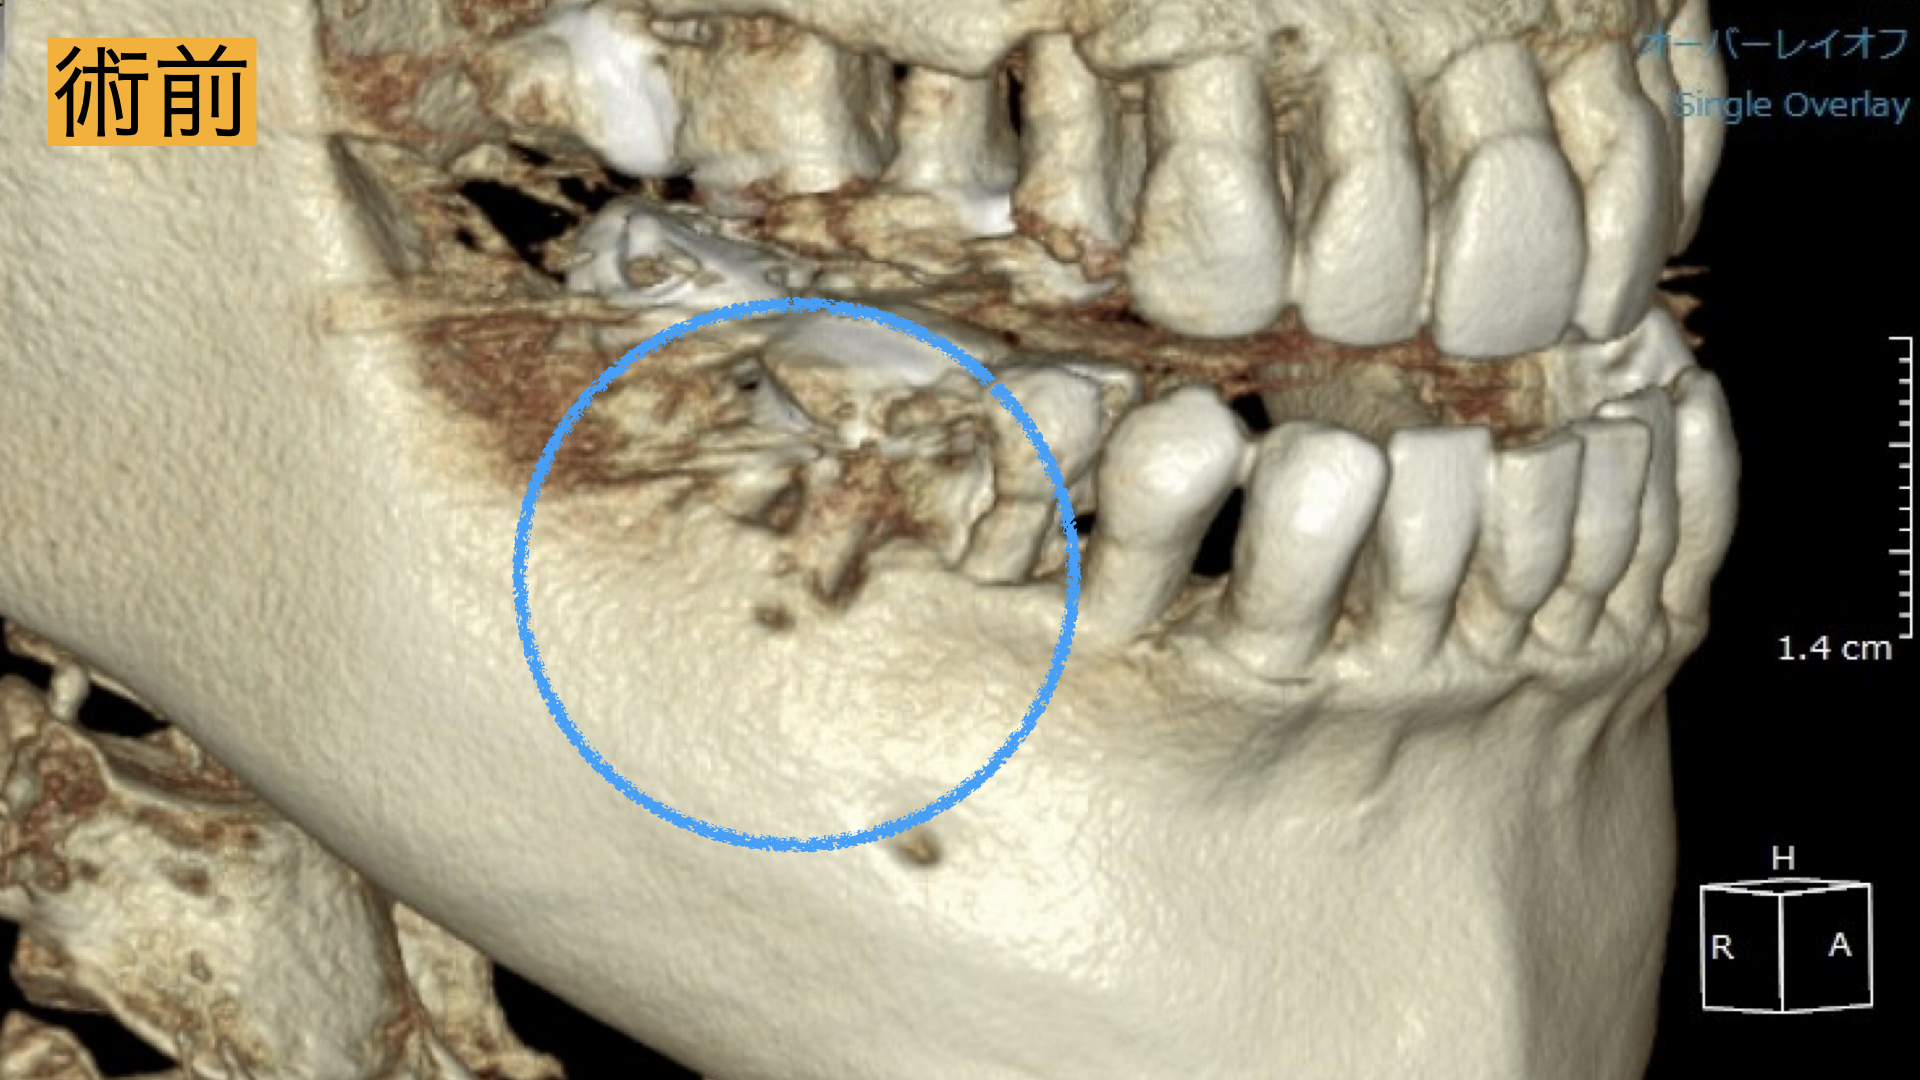

3D診断(CT)

歯科用CTは3次元の立体画像で診断することが可能です。通常のXrayは2次元の写真のため、 根管治療において複雑な根管形態を正確に把握できません。 CTでの根管形態の把握は、根管治療において必須です。

今回、根の治療が3回目とのこともあったため被せ物・土台を外して長期的予後が見込める場合は精密根管治療、見込めない場合は抜歯してブリッジ治療。と決定いたしました。